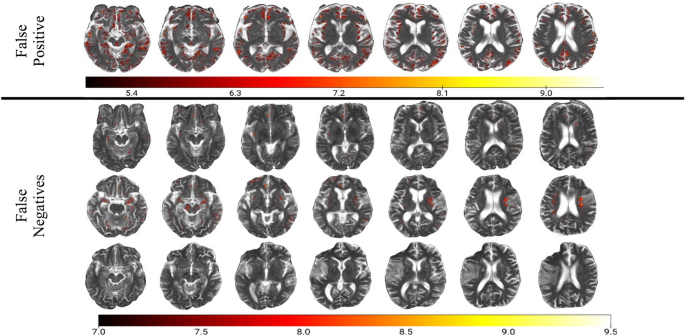

3DGradCAM revealed that midline regions, including midbrain, basal ganglia, and centrum semiovale, with high-valued activations (> 7) were indicative of severe EPVS (Fig. 2, top panel). In none-to-mild examples, fewer regions had high activations, and these lower-valued activations localized in non-relevant hyperintense tissue (Fig. 2, bottom panel). Misidentified examples suggested the distribution of class activations was the primary cause of error. In the false positive case, more tissue was resolved in the high range than in the true negative cases (Fig. 3, top row). For false negatives, less areas were resolved in the high range than in the true positive cases (Fig. 3, bottom 3 rows).

Our final model, ResNet-152, achieved an accuracy/AUC of 0.802/0.834 on the training set, 0.768/0.847 on the validation set, and 0.897(95% CI = [0.758, 0.971])/0.879 on the test set (Fig. 1, left panel) for detection of none-to-mild versus moderate-to-severe EPVS. The positive class is defined as moderate-to-severe EPVS and the negative class is defined as none-to-mild EPVS. On the held-out test set, specificity was 0.96, sensitivity was 0.80, and F1 was 0.86. The model had a positive predictive value of 92.31% and a negative predictive value of 88.46%. Accuracy was significantly higher than the NIR (NIR = 0.617; p < 0.001). There were 3 false negatives and 1 false positive (Fig. 1, right panel). In the false positive case, the model picked up on remote infarcts that resemble EPVS. Mean CLEVER score for the test set was 5.76, indicating that the model was substantially robust to noise. Supplementary table 2 shows the comparison of validation loss and accuracy for the three models that were tested (ResNet-50, ResNet-101, ResNet-152). For the best model from this process, dropout was tuned to maximize validation accuracy. The best network based on fivefold cross-validation accuracy was ResNet-152 with 40% dropout (Supplementary Table 2).